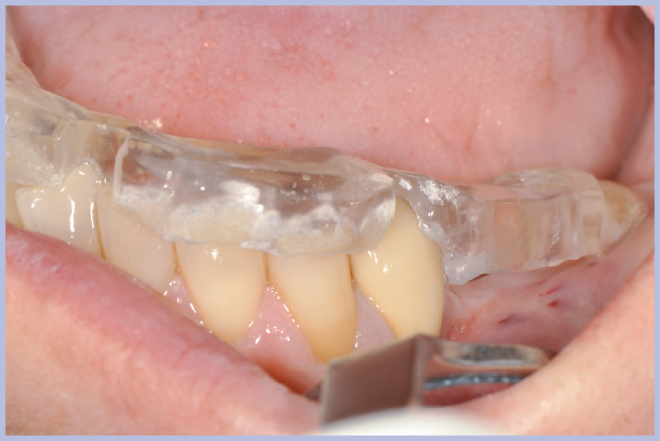

- Figg. 6, 7 – Verifica clinica della stabilità della mascherina radiologica sulla paziente

- Fig. 7